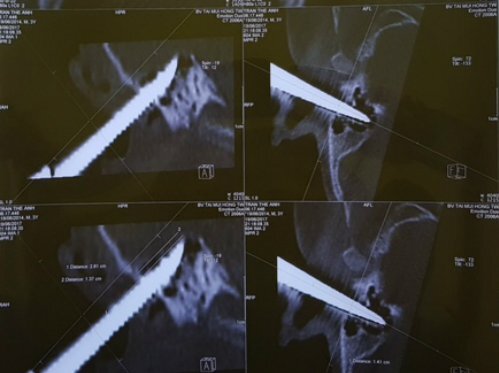

Một bé trai 2 tuổi rưỡi bị một chiếc kéo to cắm vào ống tai, sau đó được bác sĩ Bệnh viện Tai Mũi Họng Trung ương mổ rút dị vật.